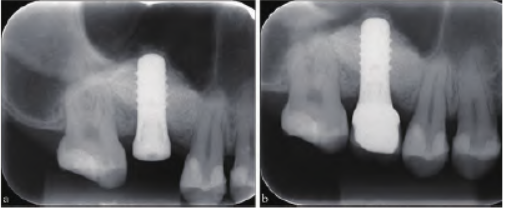

待上颌窦外提升术后10 个月于16 牙处植入士卓曼4.8 mm×10 mm RNSP TiZr 种植体(Straumann集团,瑞士) 1 枚,植入扭矩30 N.cm,旋入愈合基台,3 个月后行冠修复(图3a~b)。

图 3 患者根尖片。a:种植术后;b:种植修复后。